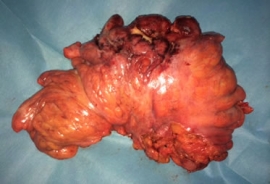

Η ελκώδης κολίτιδα είναι χρόνια, υποτροπιάζουσα, ιδιοπαθής, διάχυτη φλεγμονώδης και ελκωτική νόσος του κόλου και του ορθού. Ιστολογικά, εντοπίζεται στο βλεννογόνο και στην υποβλεννογόνια στιβάδα. Μακροσκοπικά, προσβάλλει, κατά συνέχεια ιστού, άλλοτε άλλο μήκος του παχέος εντέρου (συχνότερα ορθοσιγμοειδίτιδα, με προσβολή ορθού σε 95% των περιπτώσεων) και ολόκληρο το παχύ έντερο…